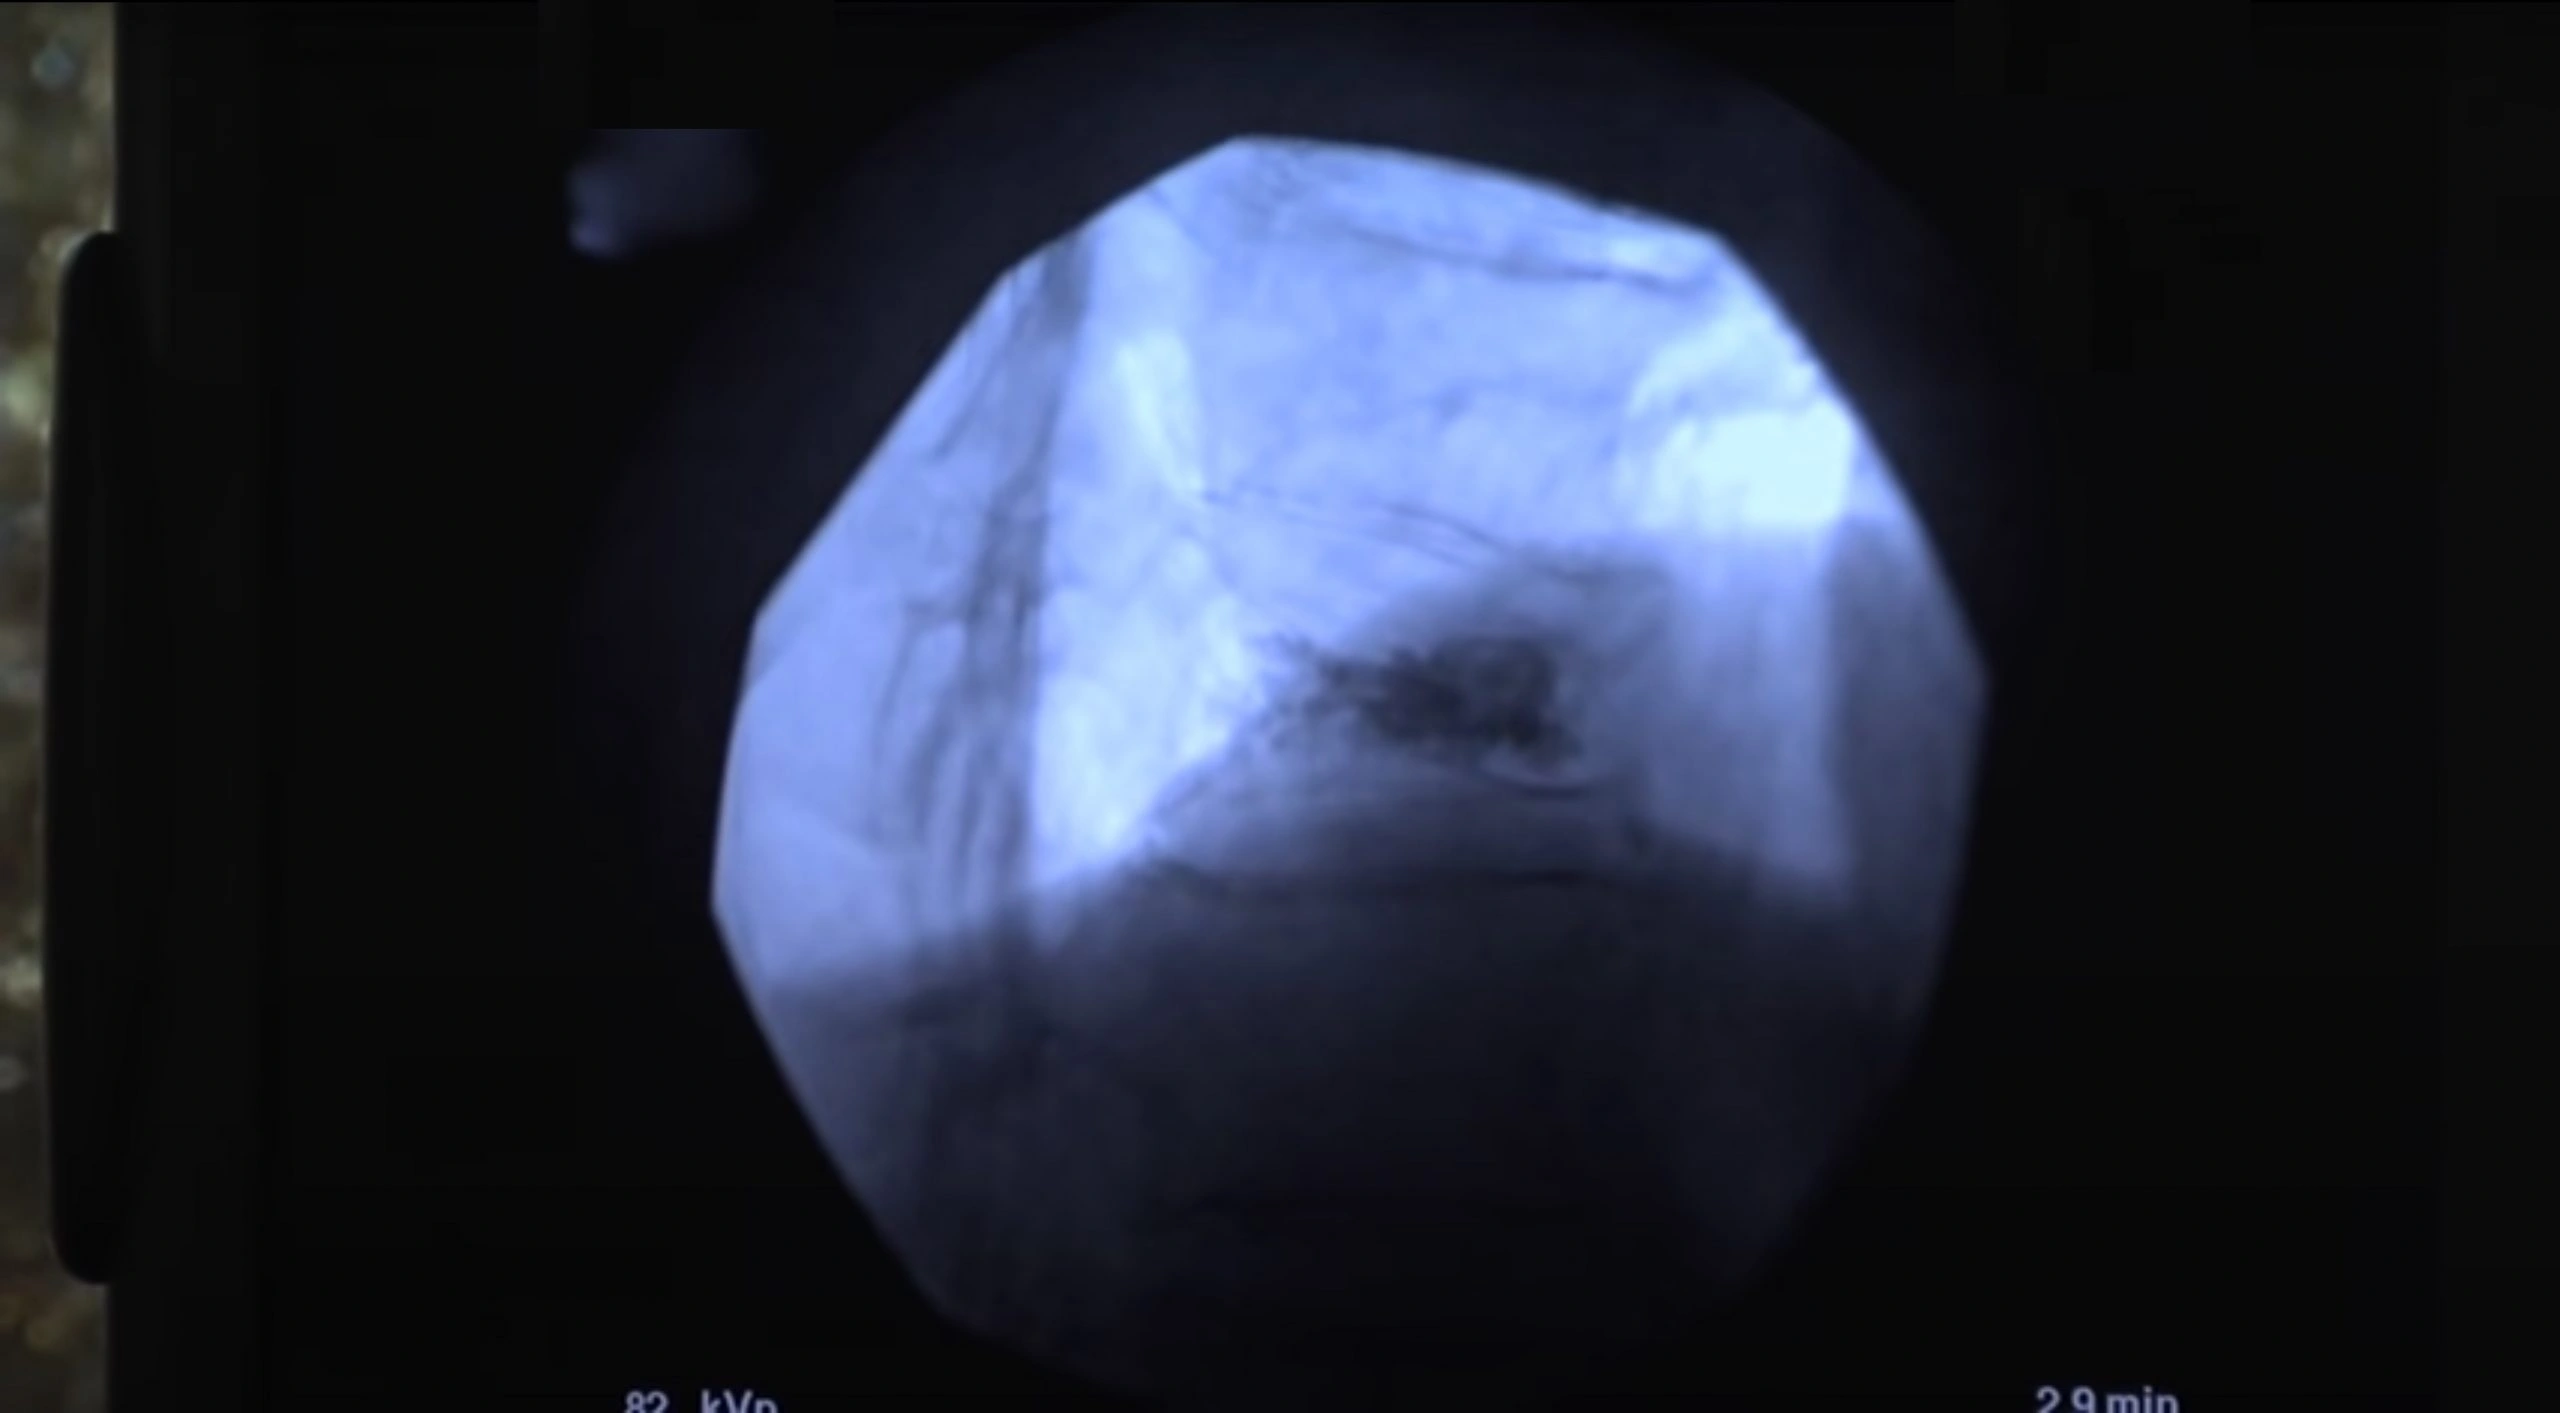

Raggiunto il corretto posizionamento dell’ago, sempre grazie all’ausilio del controllo radiologico “in-live”, si procede all’iniezione di pochi ml di cemento osseo.